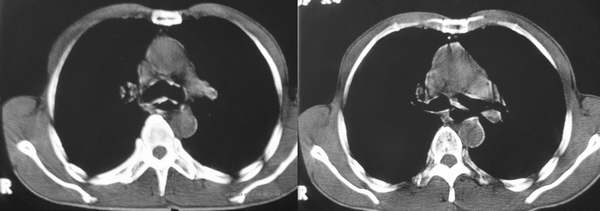

患者,男,58岁。吞咽困难3个月,胃镜示食管中、下段狭窄,右后壁隆起,黏膜表面光滑柔软无破坏。正常图象未上传

食管中下段右后壁明显增厚,管腔狭窄,考虑食管癌,做一下食道吞钡应该可以更进一步证实。

中下段管壁明显增厚,不均匀,且可见有向腔内突入的软组织,考虑食道癌.

常规考虑食道癌,但是,胃镜未发现具体病变(粘膜完整,柔软),应此,钡餐检查只能考虑为食道外压性改变,所以,增强显得较重要,建议增强ct检查,就该图片,不排除食道平滑肌瘤可能。

食管中下段右后壁软组织肿块,管腔变窄,隆突下见肿大淋巴结。考虑食管癌淋巴结转移。

结合胃镜检查,食管中下段右后壁软组织肿块,考虑食道平滑肌瘤可能。建议增强和钡透。

胃镜示食管中、下段狭窄,右后壁隆起,黏膜表面光滑柔软无破坏。\"提示并非食管粘膜的病变。而食管癌是起至于粘膜层。上述ct图像提示:食管壁较均匀地增厚,故首先考虑食管肌层的病变,平滑肌瘤、纤维瘤、神经纤维瘤、血管瘤等良性病变常为食管偏侧性肿块,食管壁局限性增厚,所以该病例应为来自食管肌层的病变的恶性病变,平滑肌肉瘤的可能性大,类癌不除外。

隆突下间隙结构不清,考虑有淋巴结肿大,並怀疑有融合,椎体前软组织块影似乎不像食管壁增厚,是否考虑有纵隔淋巴瘤,或食管壁淋巴瘤纵隔转移